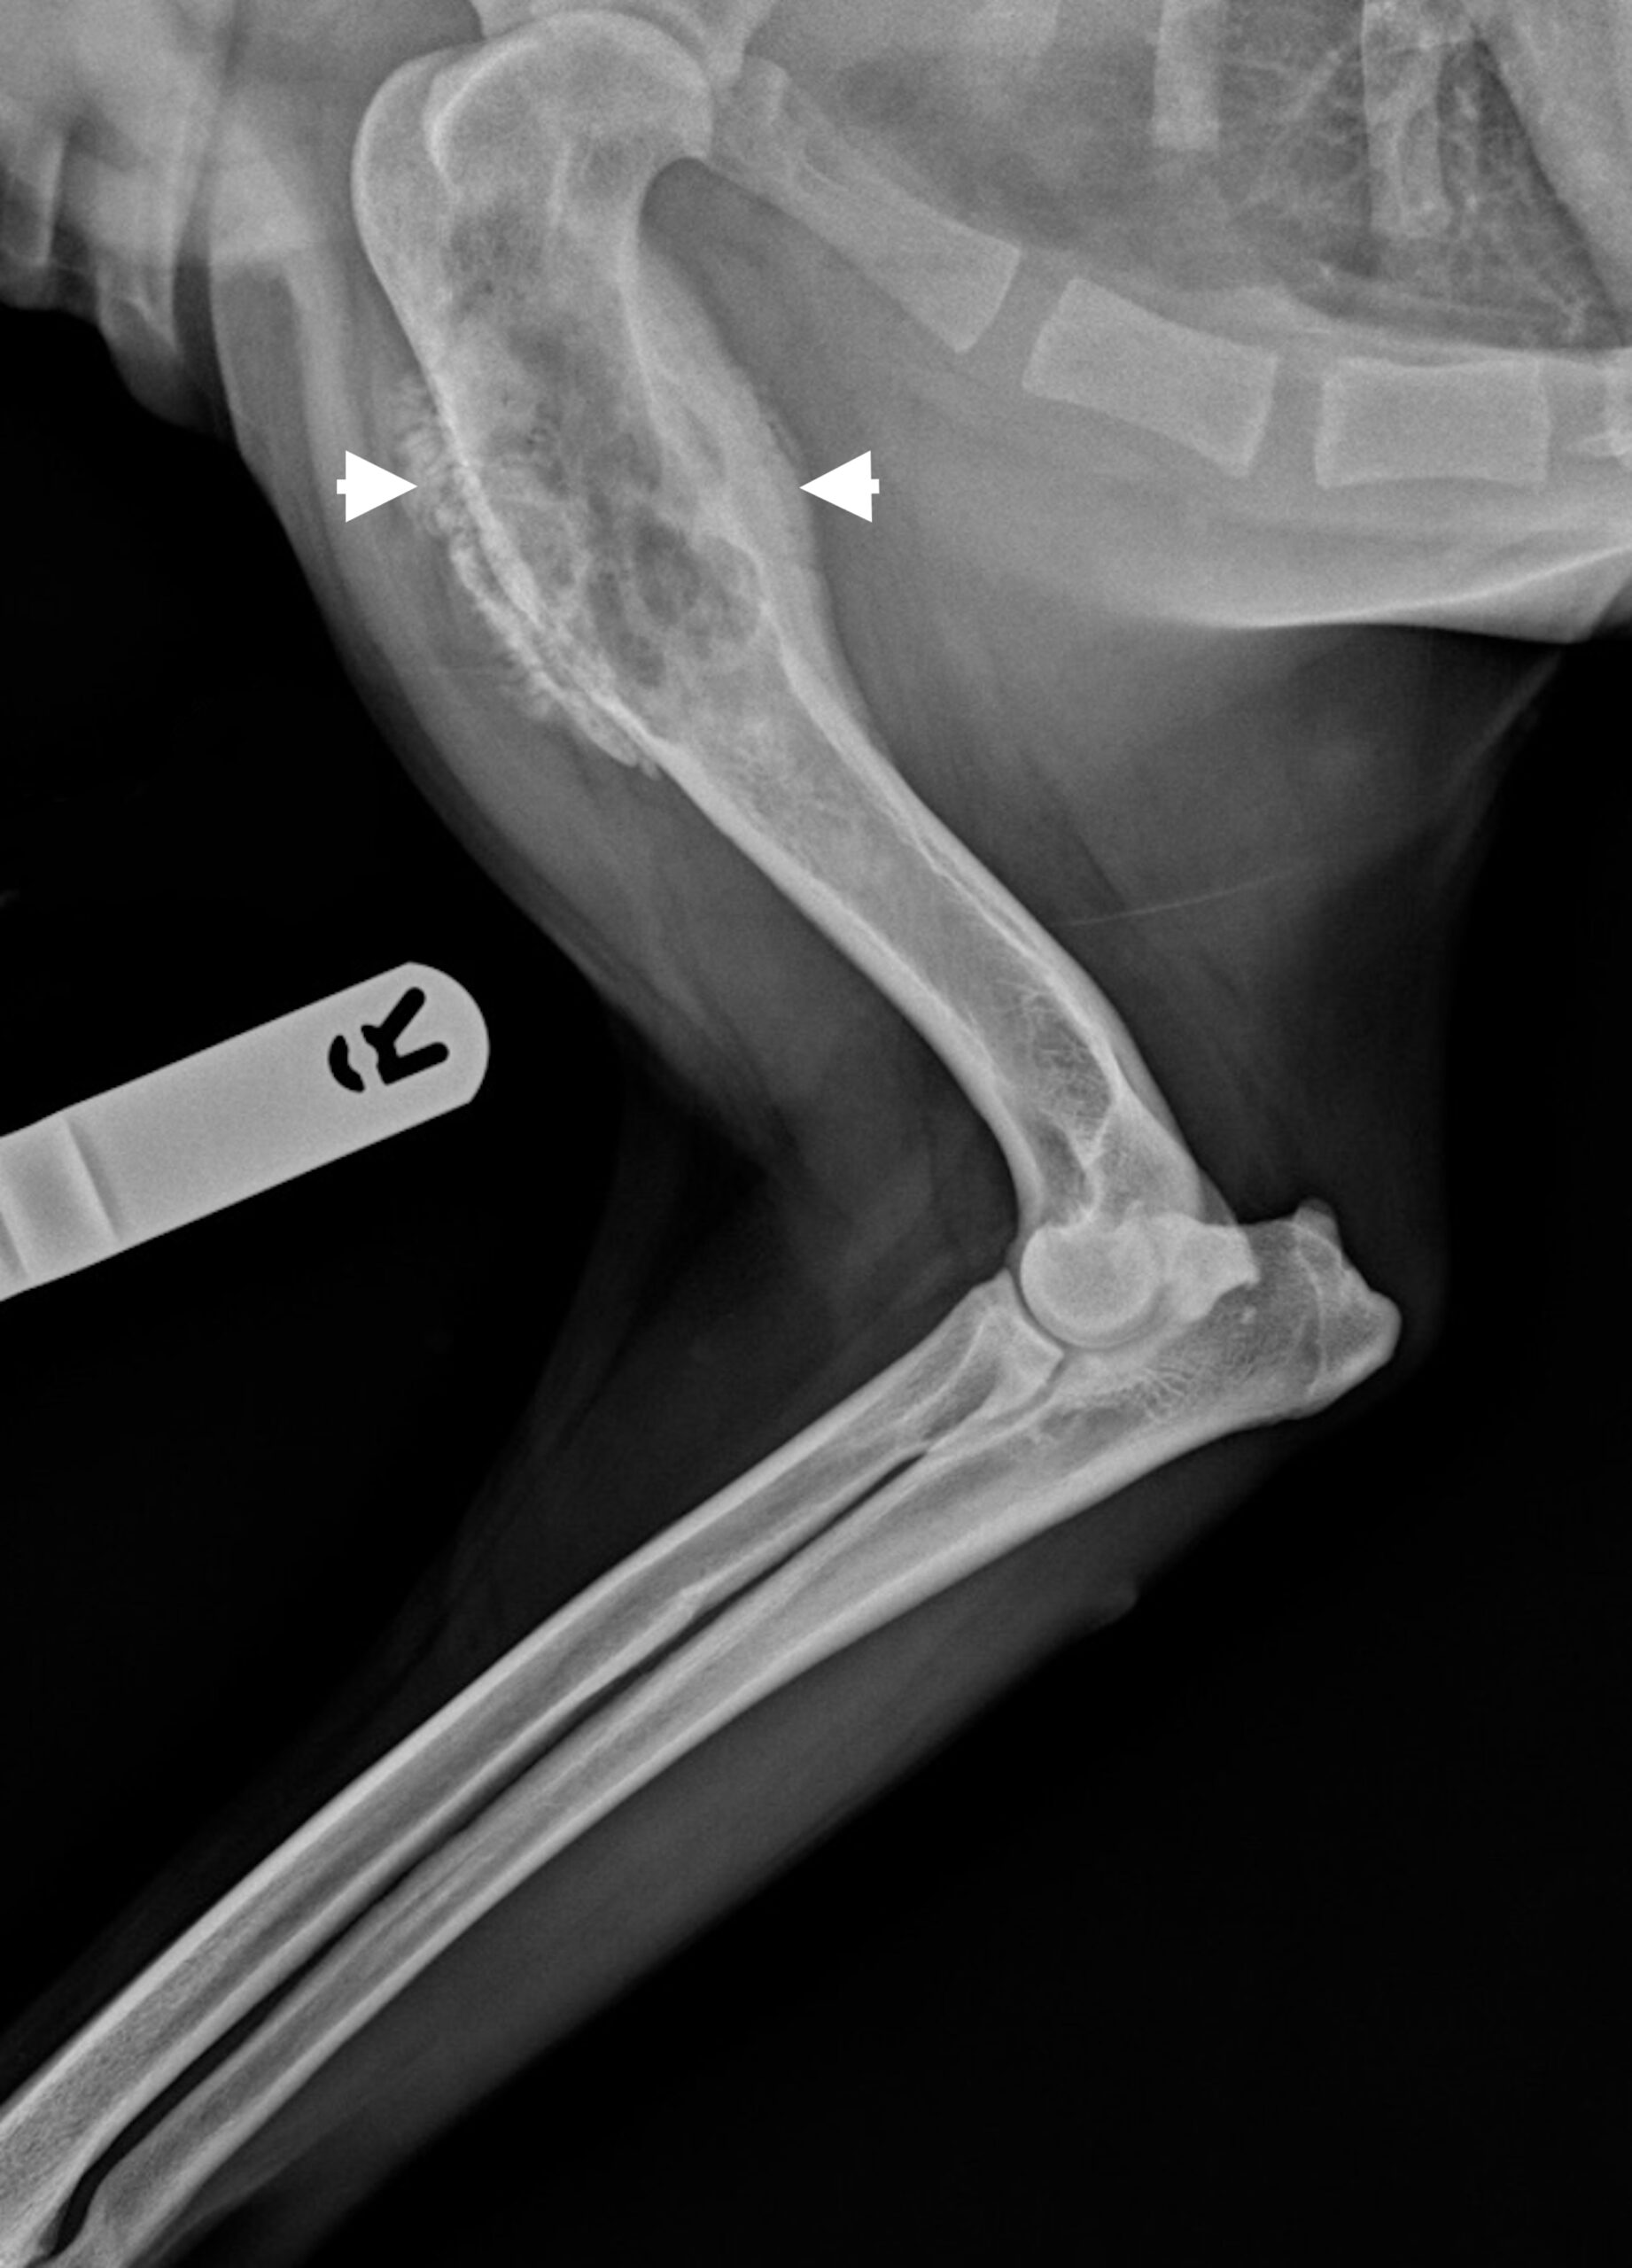

Osteosarcoma is a serious malignant bone tumour. Dogs with osteosarcoma often show signs of lameness with bony or soft tissue swelling which can be severely painful. Canine and human osteosarcoma present clinically with similar characteristics, clinical timelines and tumour biology. Therefore, studies on canine osteosarcoma can also be highly valuable in informing studies and knowledge of the disease in humans.